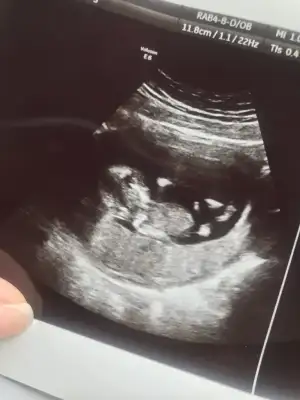

Uzun zamandır okuyorum ama ilk kez yazıyorum :) ne kadar okusamda ramzi ve nub teoirilerini anlayamadım bir türlü. Tüp bebek tedavisi sonucu hamile kaldım , sırasıyla 6 hafta,8 hafta ve son olarak 12+2 haftalık görüntülerimizi ekliyorum benim içinde cinsiyet tahmini yapar mısınız lütfen :)

• IMG_2958.webp

IMG_2958.webp

16,7 KB · Görüntüleme: 66